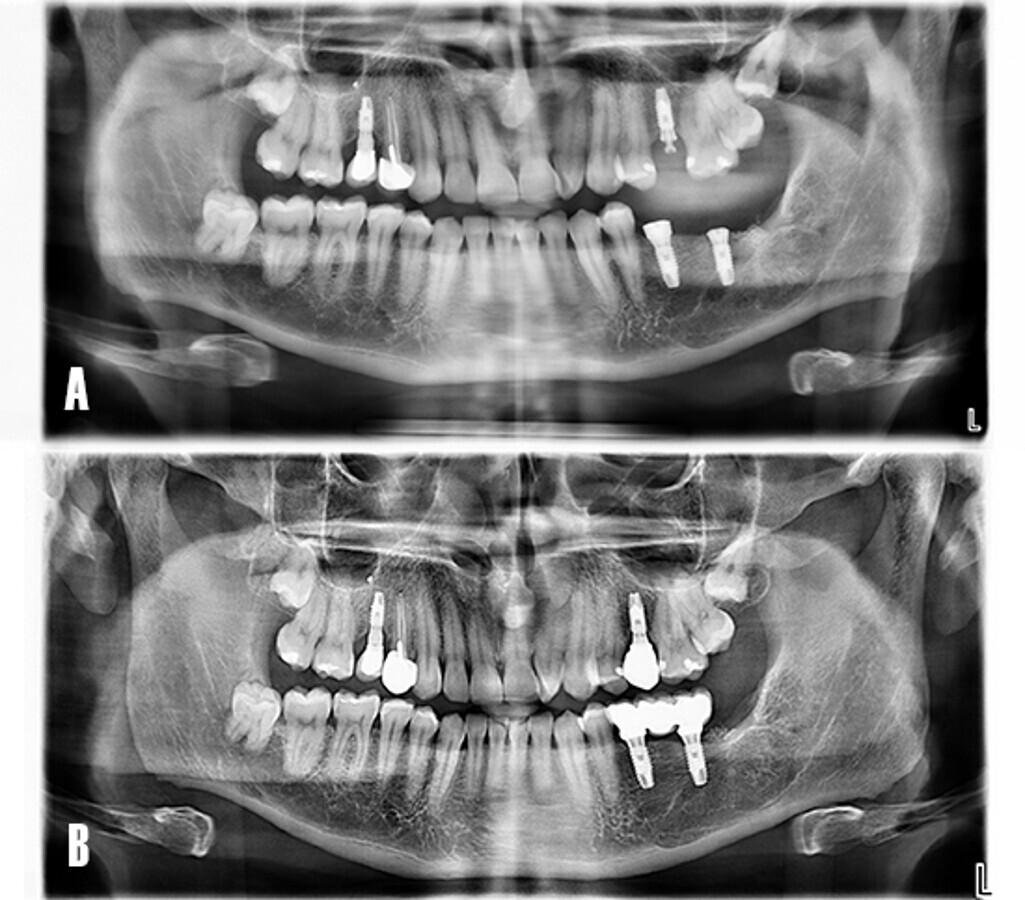

Tras realizar la evaluación radiológica bidimensional, en la ortopantomografía (Planmeca ProMax 3D Classic, Helsinki, Finland) se observó una imagen osteolítica radiotransparente que englobaba a los dientes 3.7 y 3.8 no erupcionados. Además la lesión había producido rizólisis de los dientes 3.5 y 3.6. El paciente era portador de prótesis implantosoportada a nivel 1.5 y 2.5, y había recibido tratamiento de conductos en el diente 1.4. Se observó la presencia de los cordales no erupcionados en el primer, segundo y cuarto cuadrante (Fig. 2).

Figura 2. Evaluación radiológica bidimensional. La ortopantomografía advierte la presencia de un proceso osteolítico circunscrito a las coronas de los dientes 3.6 y 3.7 no erupcionados. Nótese la reabsorción radicular de los dientes 3.5 y 3.6 debido a la extensión del proceso osteolítico en sentido antero posterior.

Se realizó el control radiográfico de la zona tratada durante 12 meses. El paciente fue evaluado de forma clínica y radiológica (Fig. 10).

Figura 10. Evolución postoperatoria. El paciente acude a consulta para control radiográfico de la zona intervenida. A) La ortopantomografía evidencia el área menos radiotransparente y sugiere una neoformación ósea de la cavidad quística a los 8 meses. B) A los 12 meses se observa un tejido más radiopaco y con trabeculado óseo, compatible con hueso en fase de maduración.

El caso fue evaluado a los 24 meses de carga funcional. El examen radiológico mostró un adecuado nivel del hueso marginal respecto al día de instalación de los implantes, así como la neoformación de la zona asociada a la patología quística (Fig. 15).

Figura 15. Ortopantomografía. A) Día de la colocación de implantes. B) A los 24 meses tras la carga funcional de los implantes.